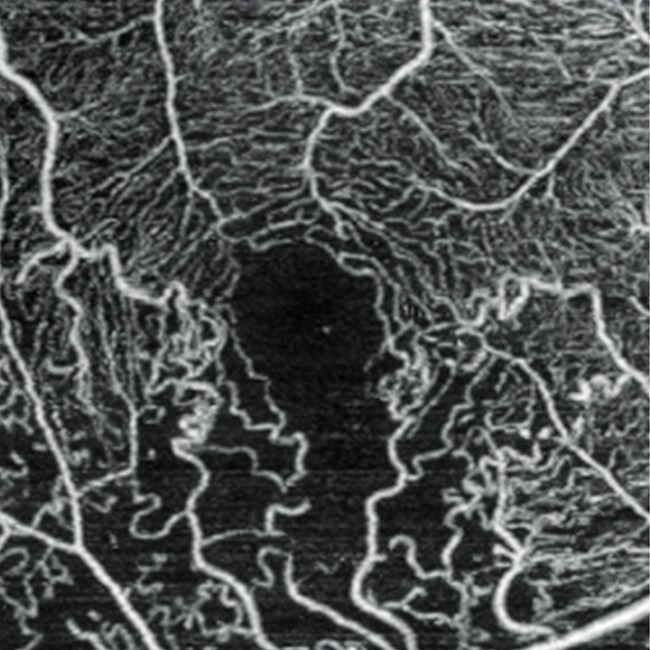

・光干渉断層血管撮影(OCTA)

上述のOCTを用いて、非侵襲的に網膜血管、脈絡膜血管を描出することができます。造影剤を使用しないので、造影剤によるアレルギーや副作用の恐れもなく速やかに検査ができます。主な対象疾患は、加齢黄斑変性、網膜静脈閉塞症、糖尿病網膜症などです。